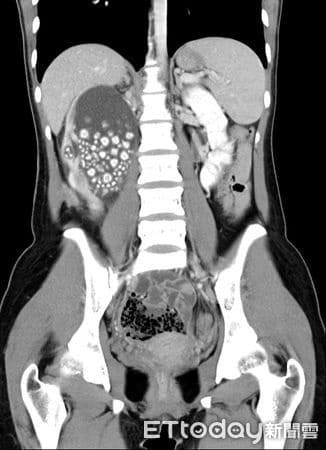

Μια 20χρονη γυναίκα, επισκέφθηκε το νοσοκομείο, νομίζοντας ότι έπασχε από απλό πυρετό και έντονους πόνους στη μέση. Αντί γι’ αυτό, οι γιατροί ανακάλυψαν πως το νεφρό της ήταν γεμάτο με περισσότερους από 300 πέτρες — τόσους πολλές, που ένας γιατρός το παρομοίασε με «ταψιά γεμάτα μικρά ψωμάκια ατμού».

Η νεαρή γυναίκα άρχισε να νιώθει έντονη κόπωση, πυρετό και πόνους στη μέση. Οι γιατροί αρχικά υποψιάστηκαν λοίμωξη του ουροποιητικού ή φλεγμονή των νεφρών — καταστάσεις που αντιμετωπίζονται εύκολα. Όμως οι αξονικές και υπερηχογραφικές εξετάσεις αποκάλυψαν κάτι απίστευτο: το δεξί της νεφρό ήταν διογκωμένο και φραγμένο με εκατοντάδες πέτρες σαν μεγάλους κόκκους άμμου σχεδόν δύο εκατοστών.

Οι περισσότεροι ασθενείς έχουν έναν ή δύο πέτρες. Η νεαρή αυτή γυναίκα είχε εκατοντάδες, που συσσωρεύονταν επί χρόνια λόγω αφυδάτωσης, μέχρι που το σώμα της κατέρρευσε. Οι πέτρες είχαν μπλοκάρει το σύστημα διήθησης των νεφρών, προκαλώντας λοίμωξη και πυρετό.

Οι χειρουργοί του νοσοκομείου πραγματοποίησαν περκοτανοσκοπική νεφρολιθοτομή, μια ελάχιστα επεμβατική διαδικασία μέσω μικρής τομής στην πλάτη. Σε διάρκεια περίπου δύο ωρών, αφαίρεσαν περισσότερους από 300 πέτρες γεμίζοντας πολλούς ιατρικούς δίσκους.

Oι πέτρες που αφαιρέθηκαν από τα νεφρά της νεαρής κοπέλας